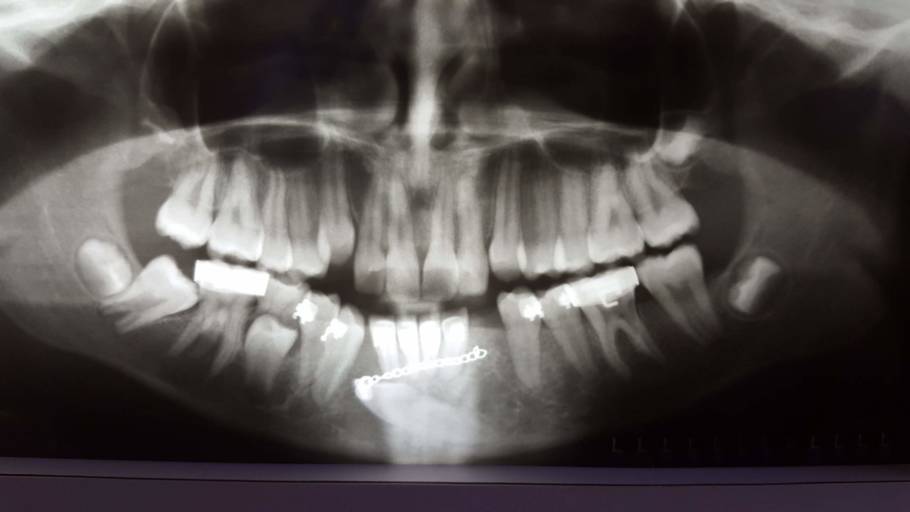

My teeth seem to be missaligned after an injury.

Hello, recently I suffered trauma to my jaw. I can close my jaw normally and my bite isn’t any different to me than before. But for the last 10 days( since the accident) I suffer from headaches every day, combined with jaw pain. Also, when I look at...

How should I fix the problem with my transmigrated mandibular canine?

I have a transmigrated mandibular canine. It is very far into my jaw. My orthodontist decided to attach a button onto the tooth, run a chain through my gums and attach it to my 2nd furthest back tooth. This constant pressure is moving the tooth into...